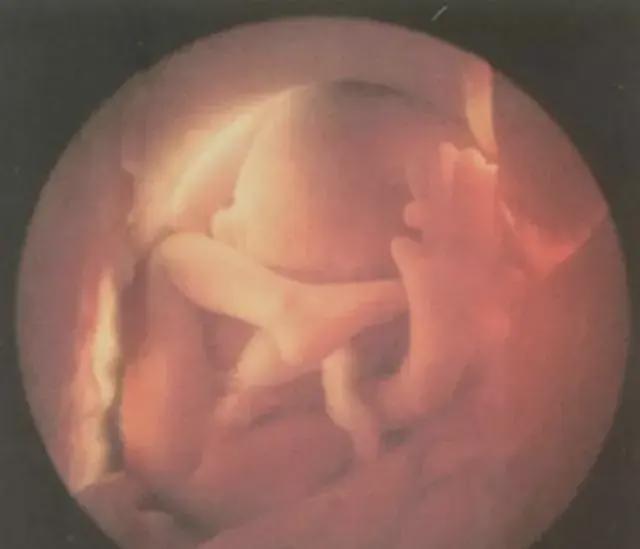

在西方医学中,羊水的专业名称是“羊膜液”。早期的西方医生在观察胎儿出生时,发现包裹胎儿的那层薄膜,与羊的肠膜结构相似,于是将其命名为“羊膜”。

后来西医传入中国,“羊膜液”这一概念被简化、汉化,逐渐演变成如今我们熟悉的“羊水”。

从成分上看,羊水98%以上是水,同时还含有少量电解质、蛋白质、激素,以及胎儿脱落的细胞等,对胎儿来说,是一个非常重要的生存环境。